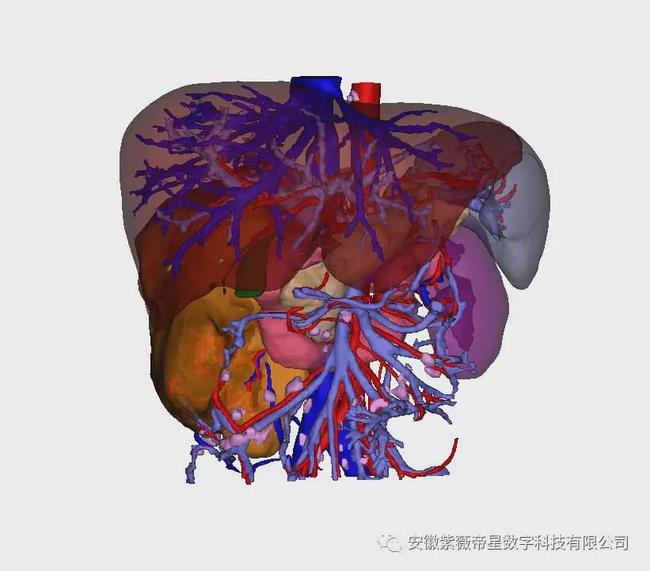

三维助力: 专家团队利用 安徽紫薇帝星数字科技有限公司 三维可视化技术对患者进行全面评估,并借助软件中的仿真模拟手术制定手术切缘,精心制定了手术方案及应急预案,成功为患者进行了肾癌手术切除。

紫薇帝星三维可视化重建结果

三维可视化全景

肾癌是多血管肿瘤,常有大的侧枝静脉,手术容易出血,且不易控制,因此肾癌手术时应争取先结扎肾动脉和肾静脉。 紫薇帝星三维可视化技术,可提前看清血供及周围组织关系,实现可视化、动态化、实时化,用于精准结扎占位周围血供血管,减少手术中出血和可能引起的肿瘤扩散,为肾癌患者点燃新希望!